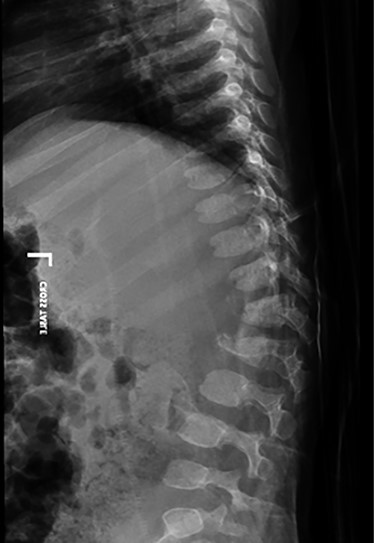

spine radiograph showing a compression fracture at T12 and L1, resulting in gibbus deformity.

A spine radiograph and CT scan (Figs 1 and 2) revealed a three-column fracture of T12-L1 and an L2 body fracture. A multiplanar and multisequential MR images (Fig. 3) of the whole spine were performed utilizing trauma protocol. The images demonstrated narrowing of the spinal canal at the level of thoracolumbar junction secondary to multilevel fractures along with myelomalacia changes involving the lower thoracic cord and conus medullaris. Additionally, the images showed an evidence of kyphosis measuring 47° at the fracture site.